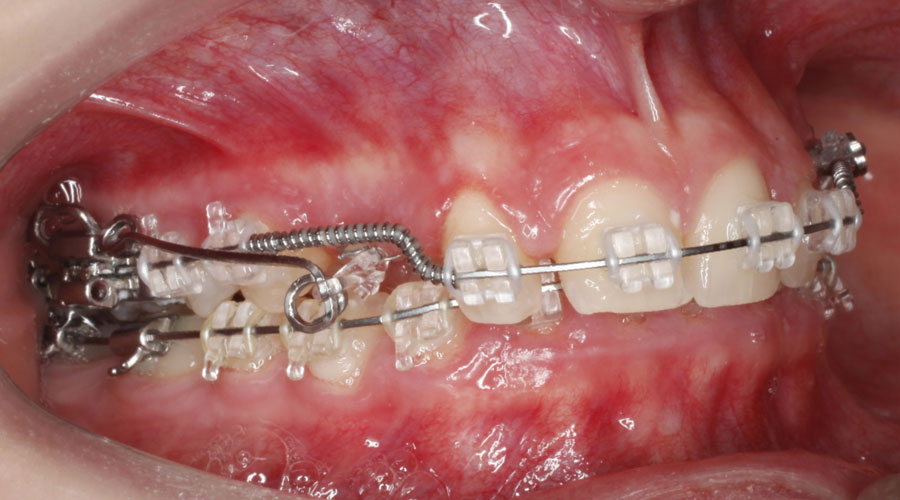

Caso clínico 2. La paciente presentaba Clase II dentaria división 2ª, con gran sobremordida, además de erupción ectópica de los caninos superiores. Se realizó ortodoncia multibracket transparentes con cirugía de fenestración de ambos caninos. Debido a la posición de éstos por palatino, colocamos dos microtornillos para ayudarnos en su tracción y poder separar la corona de las raíces de los incisivos. Posteriormente, traccionamos desde la cara vestibular con ayuda de un resorte para colocarlo en su lugar en la arcada.